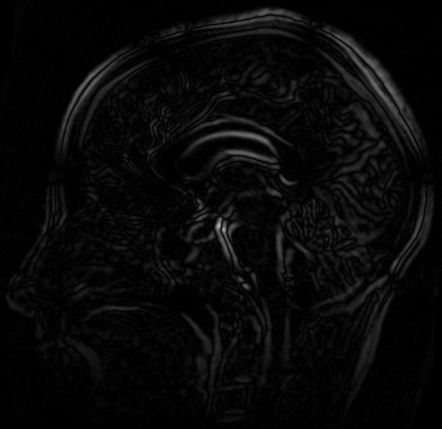

参考图像与浮动图像的差值图

参考图像与配准图像的差值图